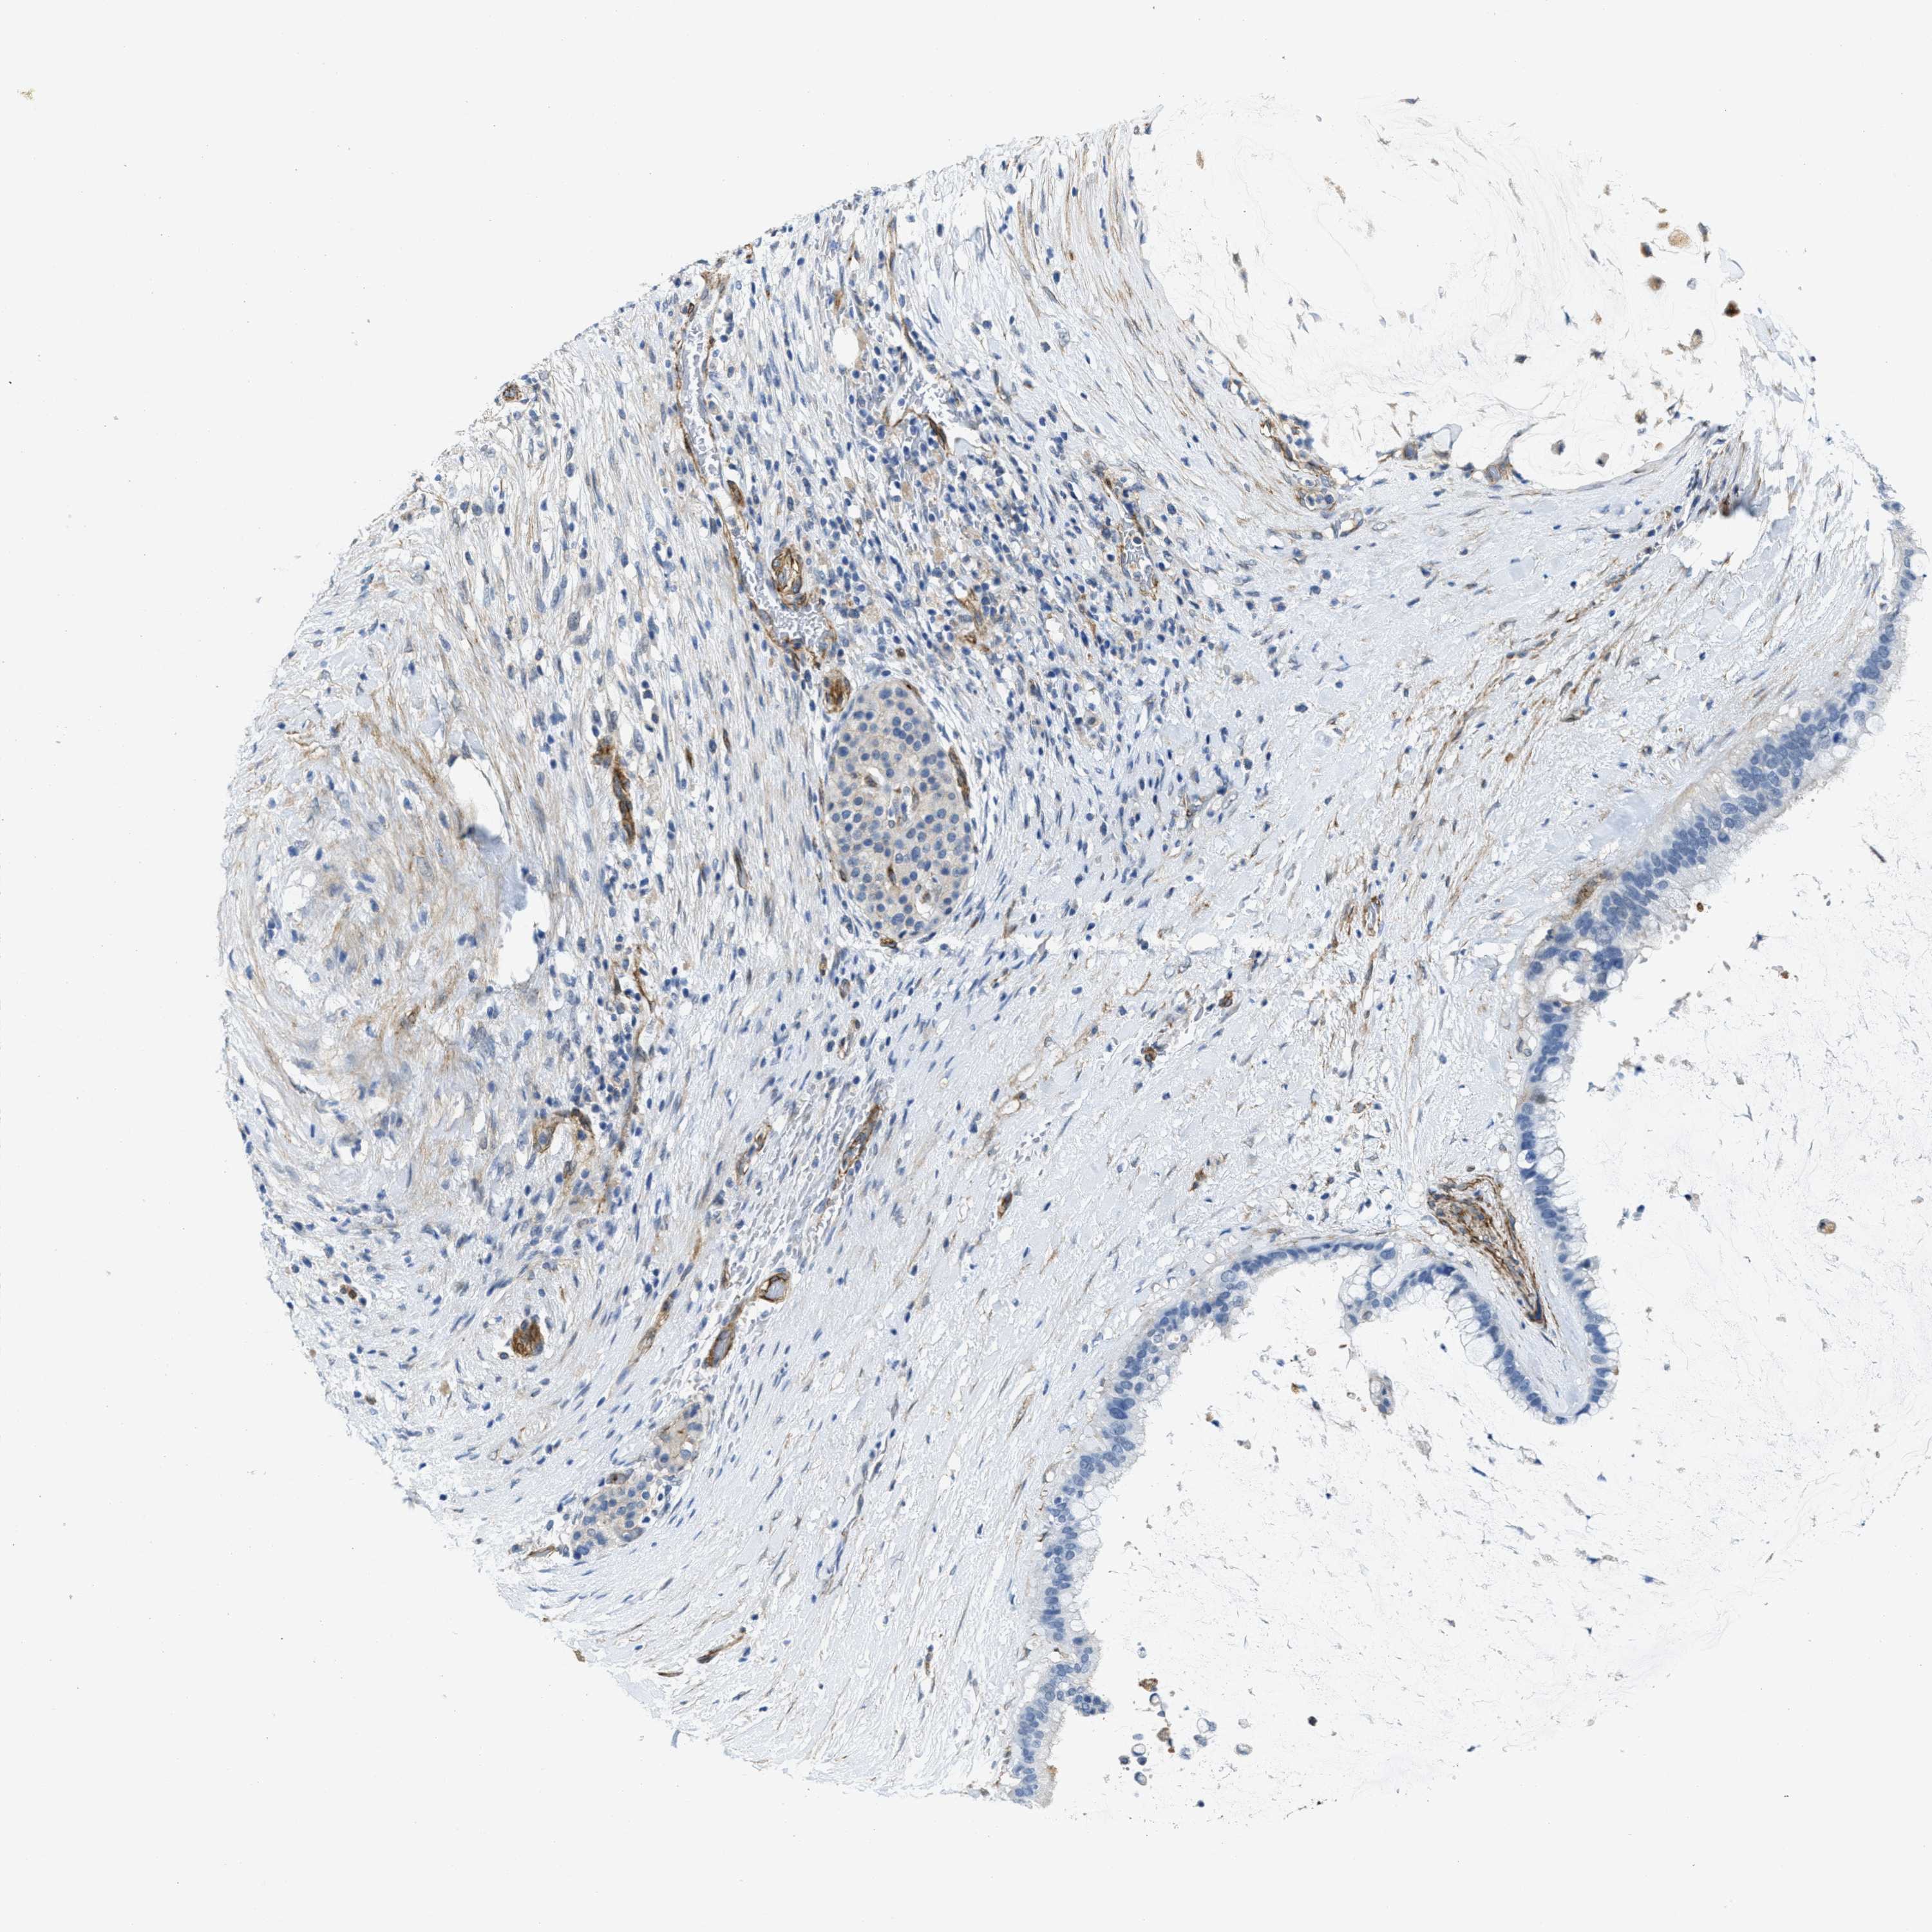

PANCREATIC CANCER - Protein expressioni

A mouse-over function shows sample information and annotation data. Click on an image to view it in a full screen mode. Samples can be filtered based on level of antibody staining by selecting one or several of the following categories: high, medium, low and not detected. The assay and annotation is described here.

Note that samples used for immunohistochemistry by the Human Protein Atlas do not correspond to samples in the TCGA dataset.

Antibody stainingi

Antibody staining in the annotated cell types in the current human tissue is reported as not detected, low, medium, or high, based on conventional immunohistochemistry profiling in selected tissues. This score is based on the combination of the staining intensity and fraction of stained cells.

Each image is clickable and will lead to virtual microscopy that enables deeper exploration of all samples and also displays staining intensity scores, fraction scores and subcellular localization as well as patient and tissue information for each sample.

Antibody HPA002738

Staining

High

Medium

Low

Not detected

Intensity

Strong

Moderate

Weak

Negative

Quantity

>75%

75%-25%

<25%

None

Location

Nuclear

Cytoplasmic/membranous

Cytoplasmic/membranous,nuclear

Adenocarcinoma, NOS